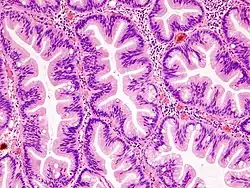

Les polypes festonnés (ou lésions festonnées) du tube digestif forment une classe de polype digestif, de localisation colorectale[1],[2],[3]. Les polypes festonnés seraient impliqués dans une voie particulière de cancérogenèse colique, la « voie des polypes festonnés »[4].

Ils sont définis morphologiquement comme des tumeurs épithéliales glandulaires polypoïdes sessiles, ou parfois planes, composées de glandes, ou « cryptes », ayant une architecture festonnée ou dentelée, avec aspect en festons ou « en dents de scie » créé par les indentations de l’épithélium bordant les cryptes. Ces lésions sont décrites dans la très grande majorité des cas dans le côlon et le rectum mais d’autres localisations digestives ont été décrites.